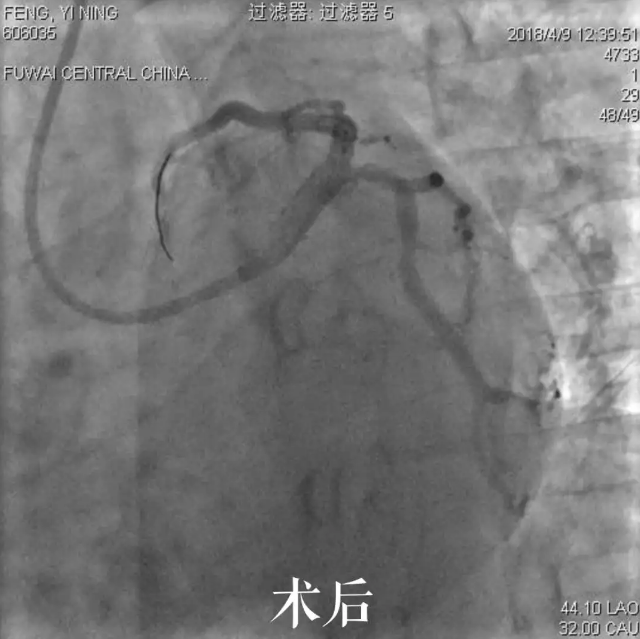

阜外华中心血管病医院副院长、河南省人民医院心脏中心知名专家高传玉教授,心内科专家齐大屯博士为小A行介入手术。造影显示心脏冠脉血管最重要的一支血管前降支近端99%狭窄,局部血流象线一样细,非常危险,随时有猝死风险。高传玉教授随即为小A植入支架1枚。术中,考虑到患者尚且年轻,为保证手术的远期效果,高传玉教授还在术中行血管内超声对病变及支架植入后贴壁情况进行了仔细评估,手术效果非常好。